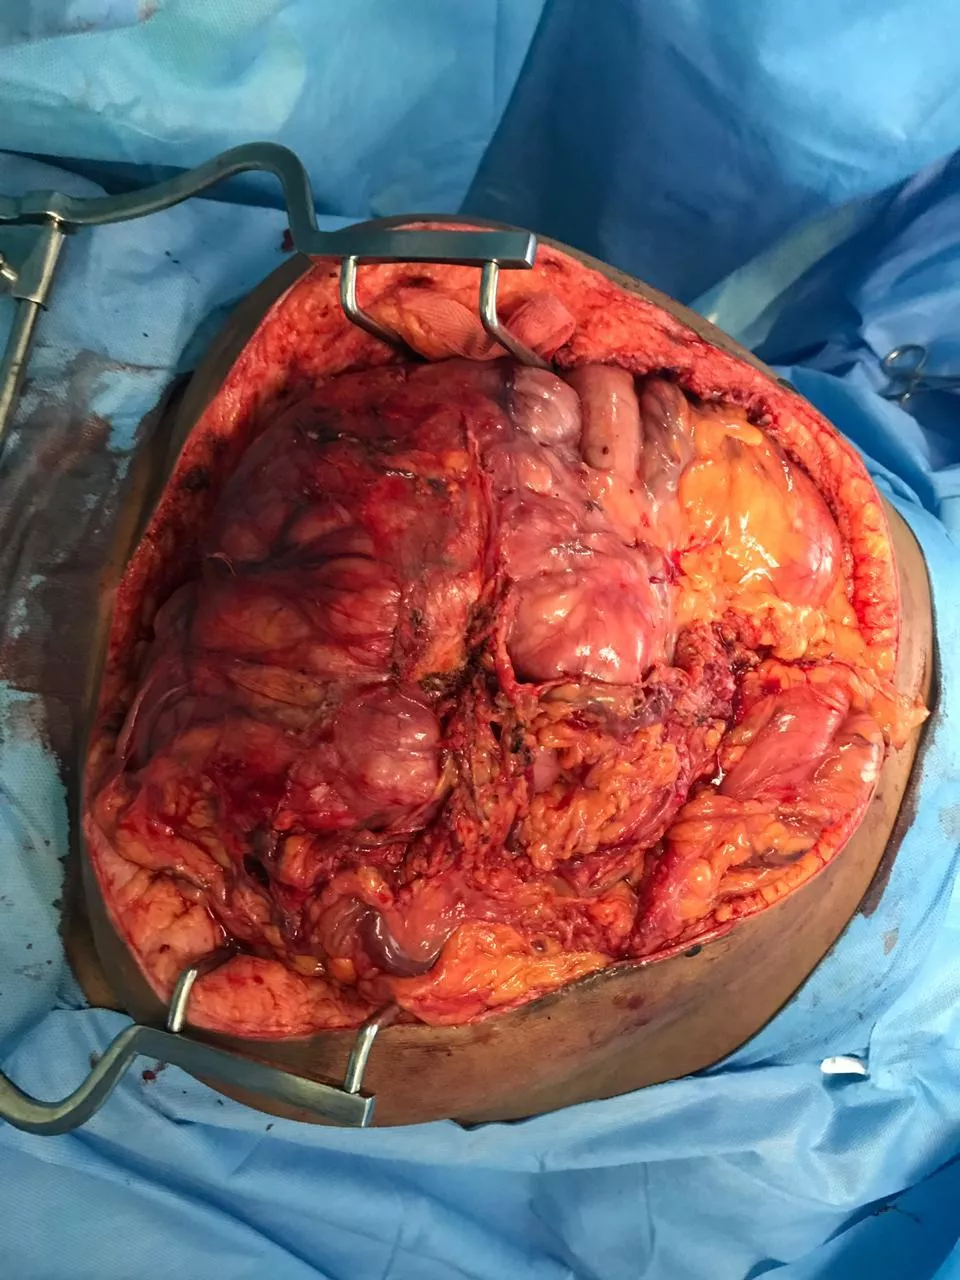

The World Record of “Largest Retroperitoneal tumour removed by surgery “is achieved by the Team of Seven Doctors (Dr. K. Sendhil Kumar, Dr. Piyush Patwa, Dr. Vimalakannan M., Dr. K. Karthik, Dr. Nivedhitha Aarthy, Dr. Venkatachalam and Dr. D. Senthil Kumar) from Coimbatore (Tamil Nadu) India on 2nd September 2019.

The Team successfully removed 7 kilograms weighing cancer tumour "Retroperitoneal Sarcoma” in 7 hours long surgery and set a new World Record for International Book Of Records.

A lady patient who was carrying a tumor for 2 years had undergone surgery at Gateway Hospitals on September 2nd, 2019. The organs were removed as a single specimen involving the right kidney, right ureter, right ovary, right colon (Cecum and ascending colon), ileum, retroperitoneal tumor, and lymph nodes. The patient survived after the major surgery.